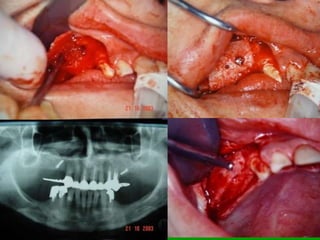

Onlay

Elevação do assoalho do seio maxilar 		(sinus lifting)

Carga mediataEnxertos ósseos

Avaliação da Altura e Largura óssea

Áreas Doadoras Retro-molares

Enxertos de mento

On Lay

Sinus Liftimg